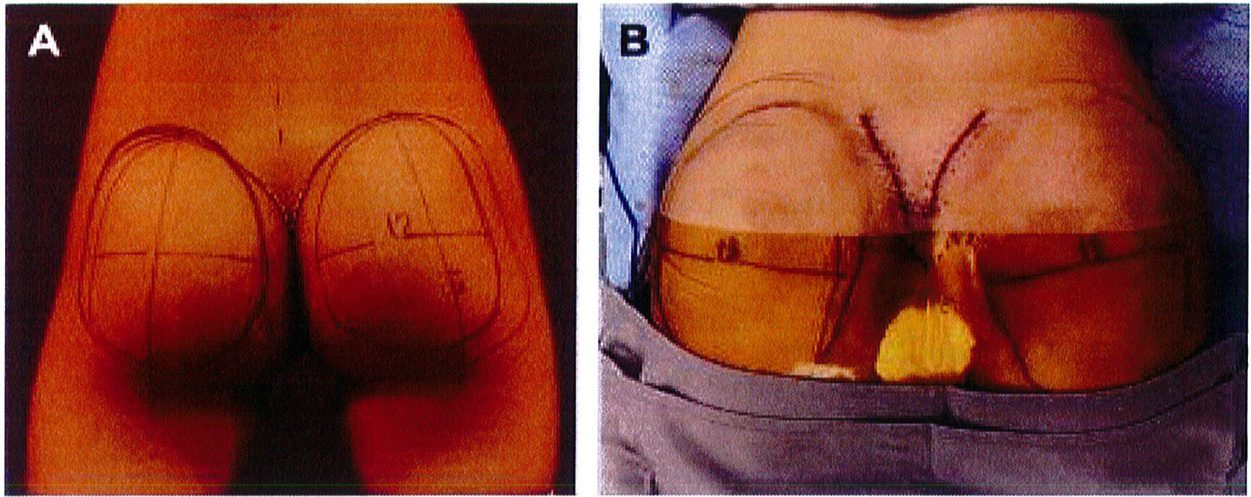

Những vấn đề mà chúng tôi đề cập trong kỹ thuật nâng mông dưới cân bao gồm các mốc giải phẫu được đánh dấu trên da trước phẫu thuật, kích thước và chất liệu khối implant.

tiêu bản như hình 4. Tiêu bản này phải được đặt chính giữa vùng mông, cách nếp lằn mông ít nhất 5cm và đường liên gai ít nhất 2cm (Hình. 5).

Bệnh nhân ở tư thế đứng, đánh dấu vị trí khối implant theo

Hình. 5. Đánh dấu vùng phẫu thuật phải tuân theo hình thể giải phẫu vốn có của từng bệnh nhân và đảm bảo rằng khối implant sẽ nằm phía ngoài xương cùng và cách nếp lằn mông khoảng 2-5 cm. (Trích từ de la Pena JA, Rubio OV, Cano JP, et al. Subfascial Gluteal Augmentation. Clin Plast Surg 2006;33:410; đã xin phép trước khi đăng tải.)

Tiêm tê dưới da bằng hỗn hợp lidocain 2% với epinephrine sau đó thêm ropivacain 7.5%. Trên lỗ hậu môn 5cm, rạch hai đường mỗi đường dài 6cm về hai phía mông cho tới khi tiếp cận được lớp cân mạc ở bờ ngoài xương cùng. Từ vị trí đó, tiếp tục rạch một đường dài khoảng 8-10 cm song với bờ ngoài xương cùng, đi lên trên và cong lõm về phía mông tương ứng để bộc lộ lớp dưới cân (Hình 8).

Hình. 8. (A) Phẫu thuật được lên kế hoạch, sử dụng các tiêu bản phù hợp với vùng mông của bệnh nhân với các đường rạch dài 6cm ở hai bên, trên vị trí hậu môn ít nhất 5cm. (B) Đây là hình ảnh bệnh nhân với tiền sử có bệnh lý liên quan vùng mông, đồng thời đã từng thực hiện hút mỡ mông trước đó, nên chúng tôi quyết định đặt đường rạch cao hơn bình thường để tránh các biến chứng.